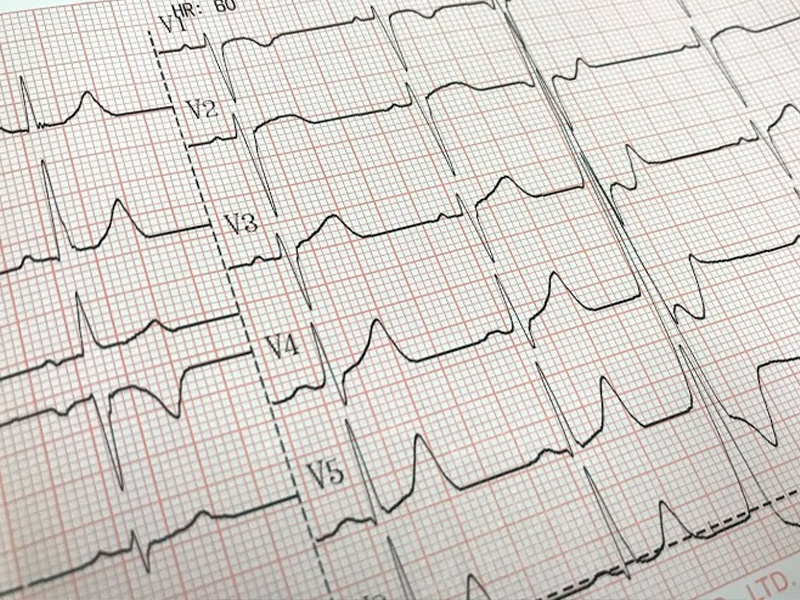

- 不整脈

心臓や血管の病気は重症化する前の治療が重要です。しかし心臓・血管の病気の多くは、初めの症状が「動悸・息切れ」「疲れやすい」などのような、加齢を伴えばどなたでも経験するような症状であるため、発見が遅れることが多いです。症状が出ることには重症化していることが多く、最悪の場合突然死につながることもあります。

そういう点で、心臓や血管の病気の治療には、早期発見につながる検査が大変重要になってきます。当院では血圧脈波検査装置や超音波エコーなどの各種検査に対応しています。予約なしで受けることができ、検査後すぐに医師が検査結果を説明させていただきます。